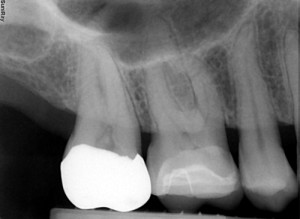

Dexis Platinum

-CMOS Sensor

-No Advertised LP/mm